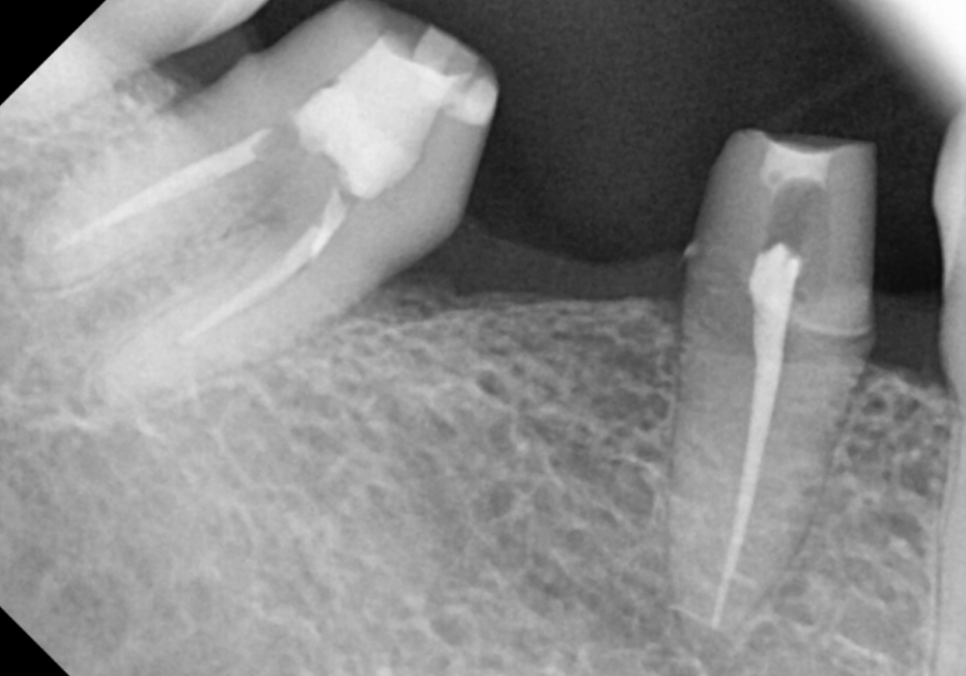

왼쪽 어금니는 맨 끝 치아가 상실된 상태라,

임플란트를 진행하기로 했습니다.

하지만 위쪽 치아가 아래로 내려온 탓에,

임플란트 머리(보철물)가

들어갈 높이가 너무 낮았는데요~

이대로 머리를 올리면 보철물이

자꾸 빠지는 부작용이 생길 수 있어요.

이럴 경우, 정출된 윗 치아를 다듬어서

#37 임플란트 머리가 들어갈 공간을

확보해야 합니다.